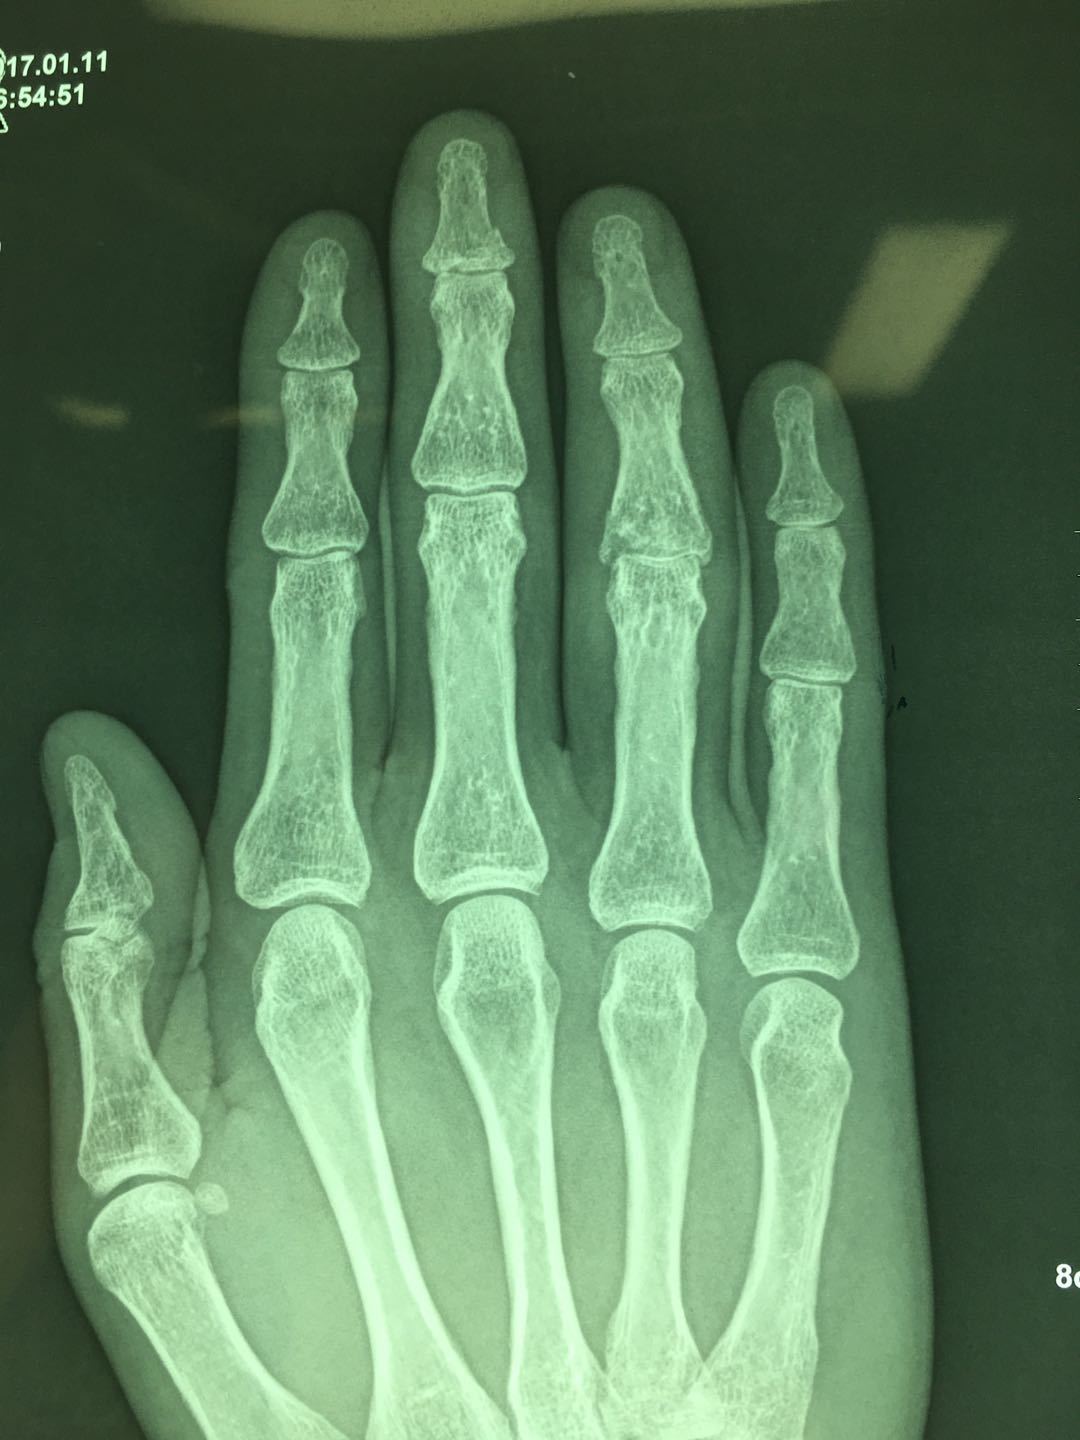

小指骨折手术-右手第五掌骨粉碎性骨折 第一个月张开手掌握拳训练 第二个月握力训练 捏网球 第三个月 感觉没什么了 就上单双杠了 附图一做完手术和三个月 —————————————————————— 这周去取了钢板,骨头上都是洞洞,同样的要恢复半年 术后一 平片提示:小指中节指骨颈部 3 型骨折。同样因闭合复位效果不满意改行手术治疗。具体过程如下。 图 2 小指指骨颈部骨折 3 型 a:正位片;b:侧位片 方法 先在透视下行闭合复位。行纵向牵引后将向背侧移位的指骨头向掌侧推挤(图 3),并保持骨折端复位。

平片提示:小指中节指骨颈部3型骨折。同样因闭合复位效果不满意改行手术治疗。具体过程如下。 图2 小指指骨颈部骨折3型。(a)正位片(b)侧位片 方法 先在透视下行闭合复位。行纵向牵引后将向背侧移位的指骨头向掌侧推挤(图3),并保持骨折端复位。你好,在战斗过程中,如果一侧手指骨折,打钢钉做手术,需要补偿精神损失和营养吗? 咨询时间: 1605 湖北 恩施州 交通事故 打架造成轻伤,小指骨折需要手术。被判刑需要多长时间 咨询时间: 湖北神农架林区劳动争议 我也要提问当前在线律师23,564位,如遇类似法律问题,立即咨询